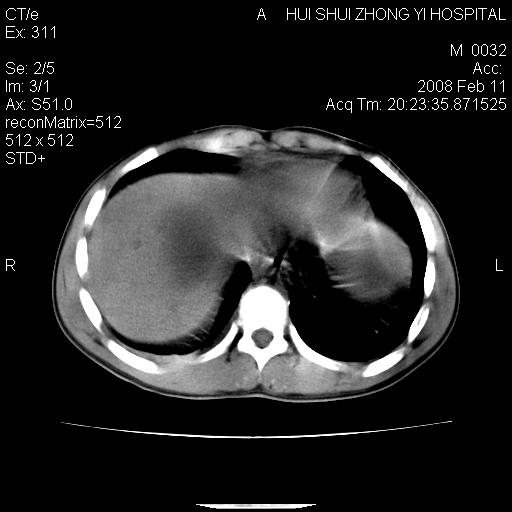

8年前曾在贵洲省人民医院b超诊断为肝内胆管结石。现腹痛剧烈,现发烧、头痛、恶心呕吐县医院b超示胆囊肿大大小159*46mm,囊内见6*5mm强回声光团,胆各总管内径56mm。提示:胆囊结石、急性胆囊炎、胆总管重度扩张。

胆囊结石.急性胆囊炎.重度胆管扩张.右侧胸腔少量积液,建议ct增强

考虑先天性胆管囊肿;胆囊增大并结石。右侧胸腔少量积液,建议ct增强。

caroli囊肿并囊内结石。胆囊增大并胆结石。典型!

先天性胆管囊肿,胆囊结石、胆囊增大,右侧少量胸腔积液。